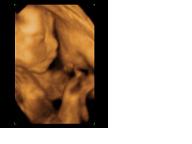

Képzeljétek, tegnap épp a Lotz Károly utcában jártam, és elcsábultam egy 4D-re :) Noel nagyon tündéri volt. Folyton a kukiját mutogatta :D Már 658 g!!! Nem sok az egy kicsit? Bár épp tele volt a pocija :)

Teszek fel két képet. A kis kéz-láb csomagos a kedvencem. Még a pici pofiját is lehet látni :)

Sziasztok! Sonny, tündéri a babád, gratulálok hozzá!

Mi vasárnap voltunk újabb 4D-n, most már bizonyossággal mondták, hogy kisfiút várunk. Meg tudtam azt is, amit eddig nem értettem, hogy miért van ekkora minőségi különbség 4D és 4D között... A válasz a magzatvíz mennyiségében rejlik, a szaki elmondása szerint, minél több víz van jelen, annál kontúrosabb, élesebb a kép. Végülis logikus, de erre sosem gondoltam.